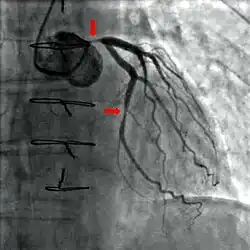

- aortální stenóza zasahující aortu, typicky v místě aortální chlopně;

- arteriální stenóza zasahující tepny, např. stenóza renálních tepen zasahující tepny vedoucí do ledvin;